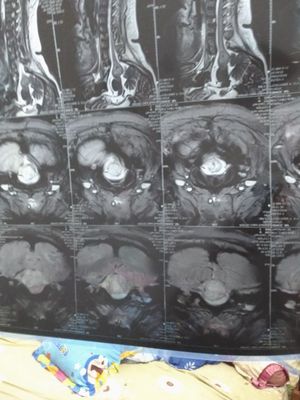

Guys i need to ask all of you, i dont know anything about this its MRI my mom and she's already die... 1 month ago. I want ask the doctor indonesia cant handle my mom diagnosis because its hard to OP its real?